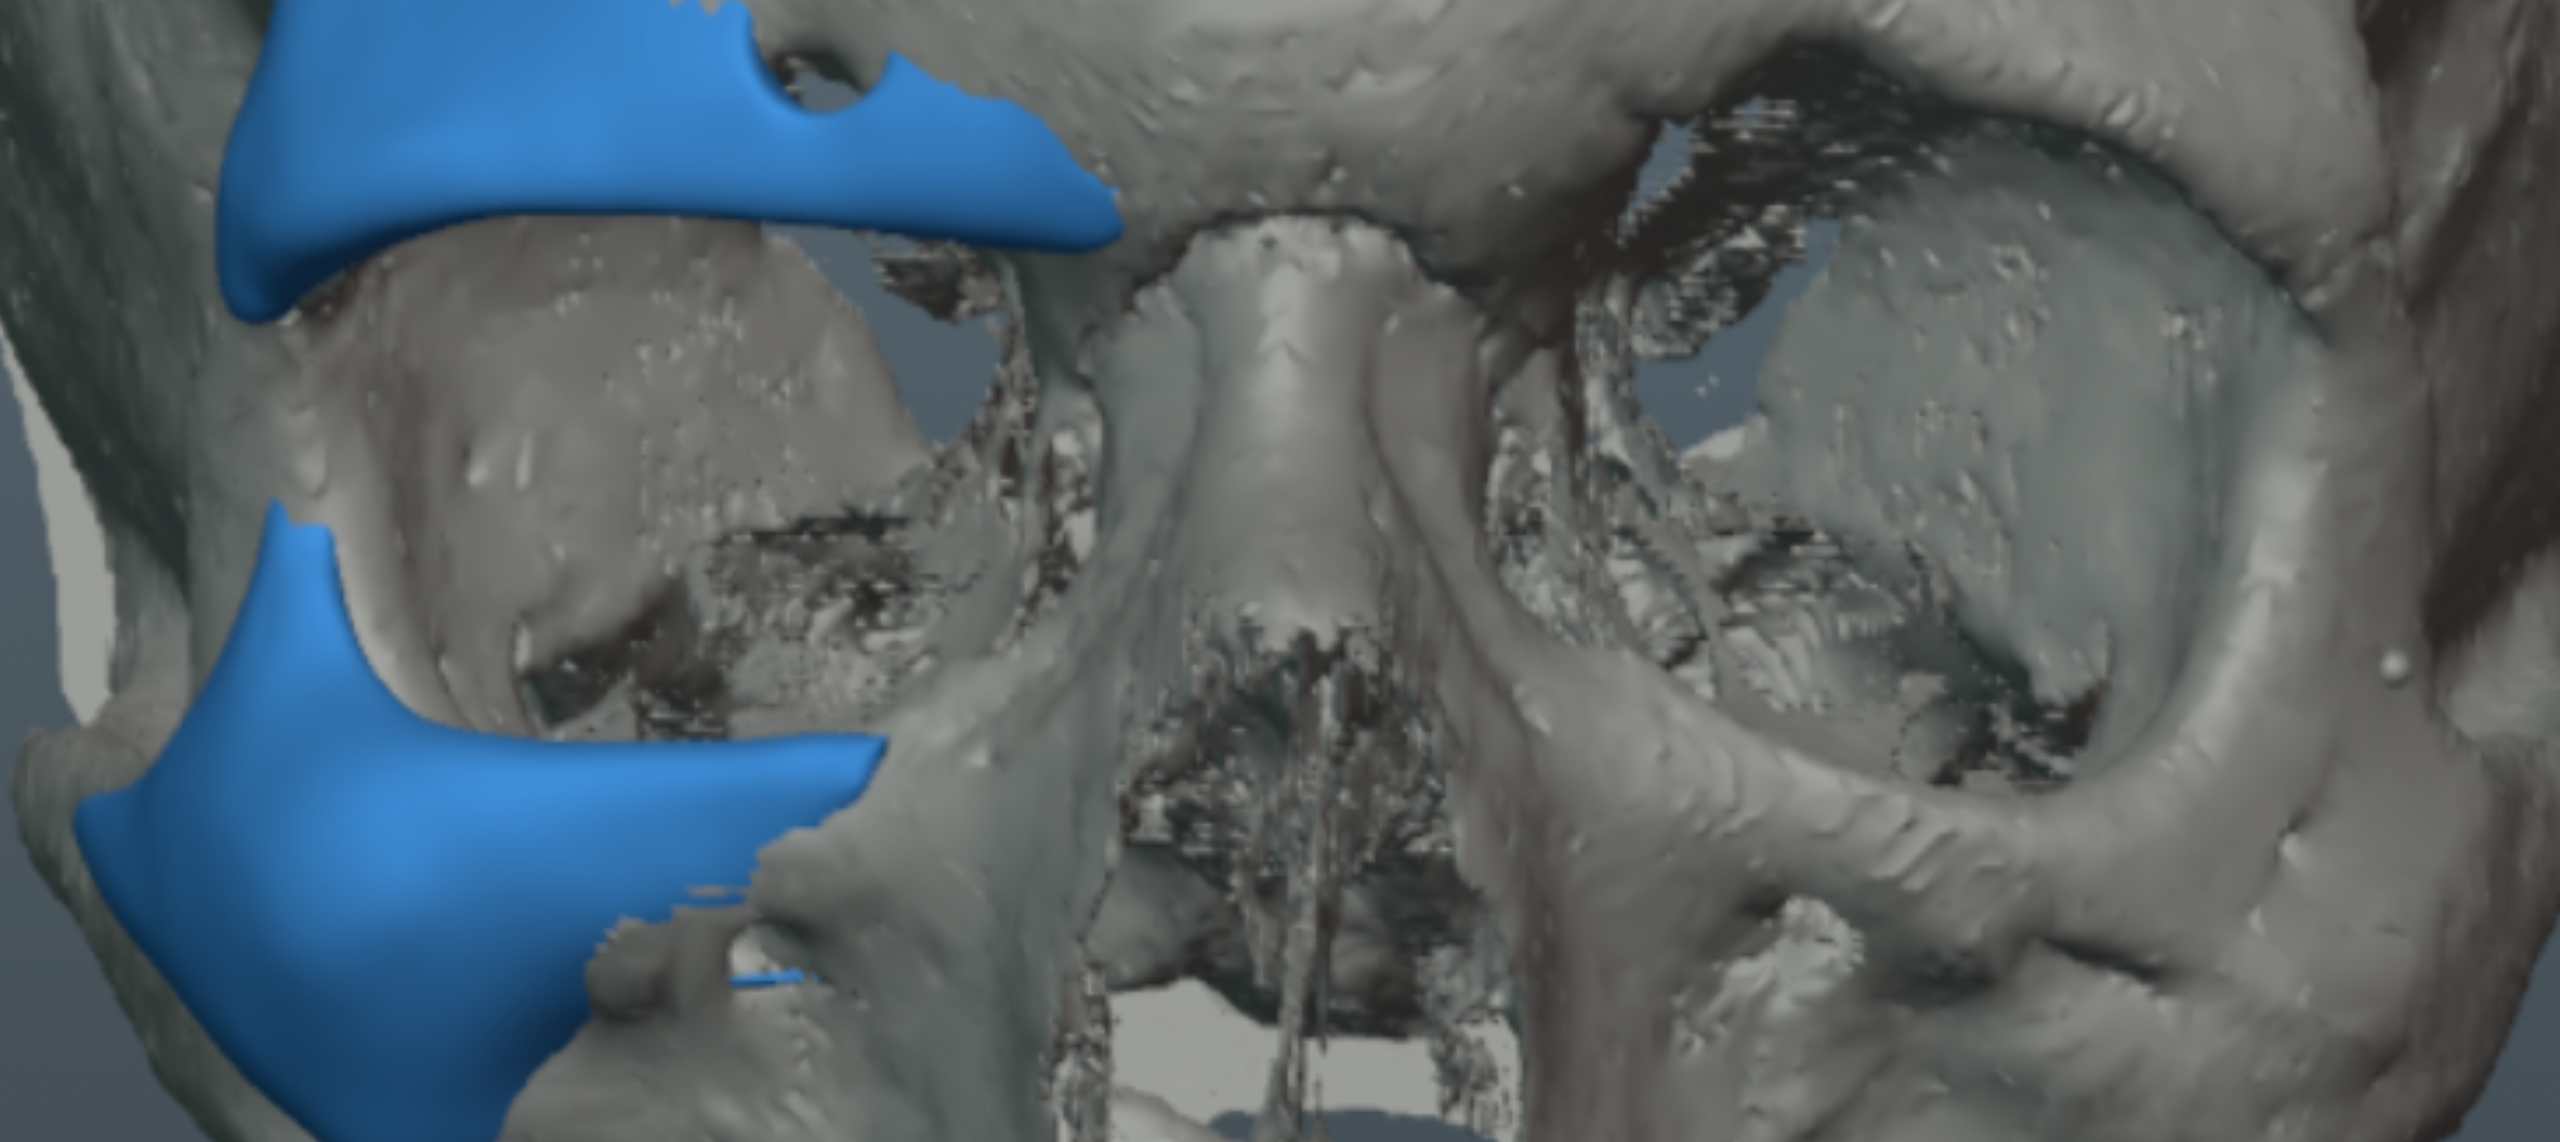

CBCT RENDERS

All attached. Frontal bone, left lateral, right lateral, soft tissue overlays, volume renders at different thresholds. The full skull, nothing hidden, nothing frauded with angles. You can see every problem I just described for yourself.

CBCT RENDERS

All attached. Frontal bone, left lateral, right lateral, soft tissue overlays, volume renders at different thresholds. The full skull, nothing hidden, nothing frauded with angles. You can see every problem I just described for yourself.